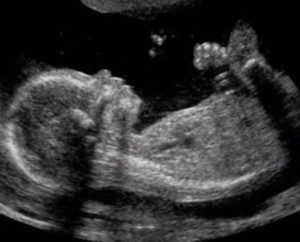

Женщина может получить протокол и фото результатов УЗИ на 16,17 неделе беременности. На основании данных врач формирует биофизический профиль плода.

Плод свободно передвигается в амниотической жидкости. На крохотных ручках и ножках сформировались пальчики, которые мама сможет увидеть на фото УЗИ. Ребёнок демонстрирует великолепную мимику, рефлекторно гримасничая и улыбаясь. Зевающий малыш – прекрасный момент, который может запечатлеть фотография.

На 16-й недельке беременности малыш в матке у мамы уже размером с небольшой грейпфрут: весит около 90 гр, в длину – 110-116 мм.

У него все больше укрепляются мышцы, шея уверенно держит головку, и ребеночек пытается вертеть ей из стороны в сторону. Тренирует он и остальную мышечную систему: дергает ручками-ножками, пробует переворачиваться.

Ножки плода становятся все длиннее, на пальчиках появляются полноценные ногти.

Он уже двигает веками, кривляется, строит рожицы, пытаясь выразить радость или возмущение.